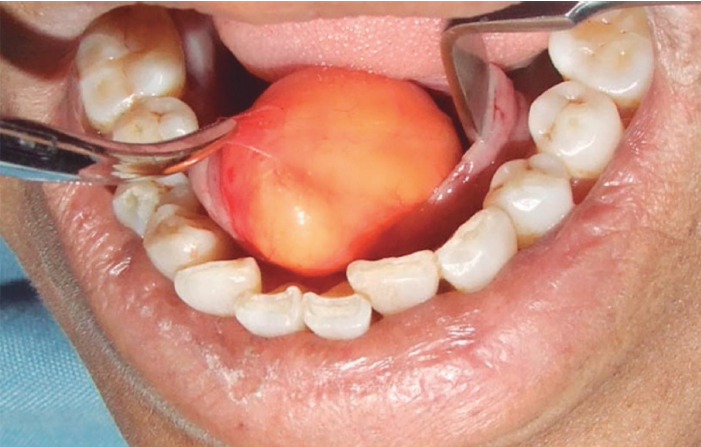

peripheral ossifying fibroma

not confused with “peripheral odontogenic fibroma”

relatively common reactive lesion, probably arising from periodontal ligament

unrelated to the central ossifying fibroma

exclusively on the gingiva

maxilla> mandible

frequently ulcerated

peripheral ossifying fibroma treatment and prognosis

local excision down to the periosteum

elimination of local factors or irritants

approximately 16% recurrence rate